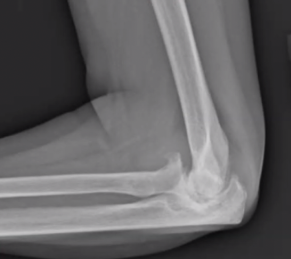

Elbow arthritis is an uncommon but debilitating condition that causes pain, stiffness, and reduced function in the elbow joint. Unlike arthritis in other joints, elbow arthritis often preserves joint cartilage while developing hypertrophic osteophytes (bone spurs) and capsular contracture. The condition primarily affects middle-aged men engaged in heavy manual labor or athletic activities.

– X-rays to evaluate joint space, osteophytes, and bone changes